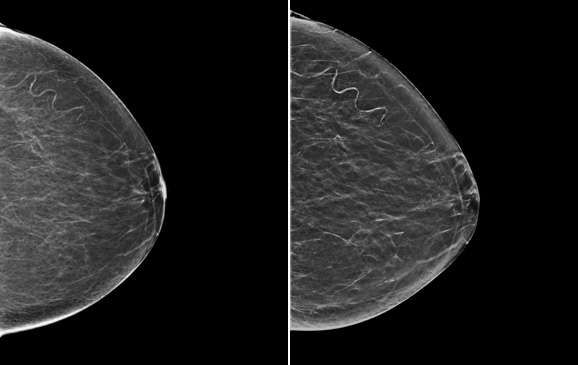

Figure 2. Two digital breast tomosynthesis “slices” from the same patient as in Figure 1. In the left image, the vascular calcifications are partially blurred because they are out of plane. In the right image, the vascular calcifications along part of the tortuous vessel are in plane and clearly seen, while the remainder of the vessel is out of plane.